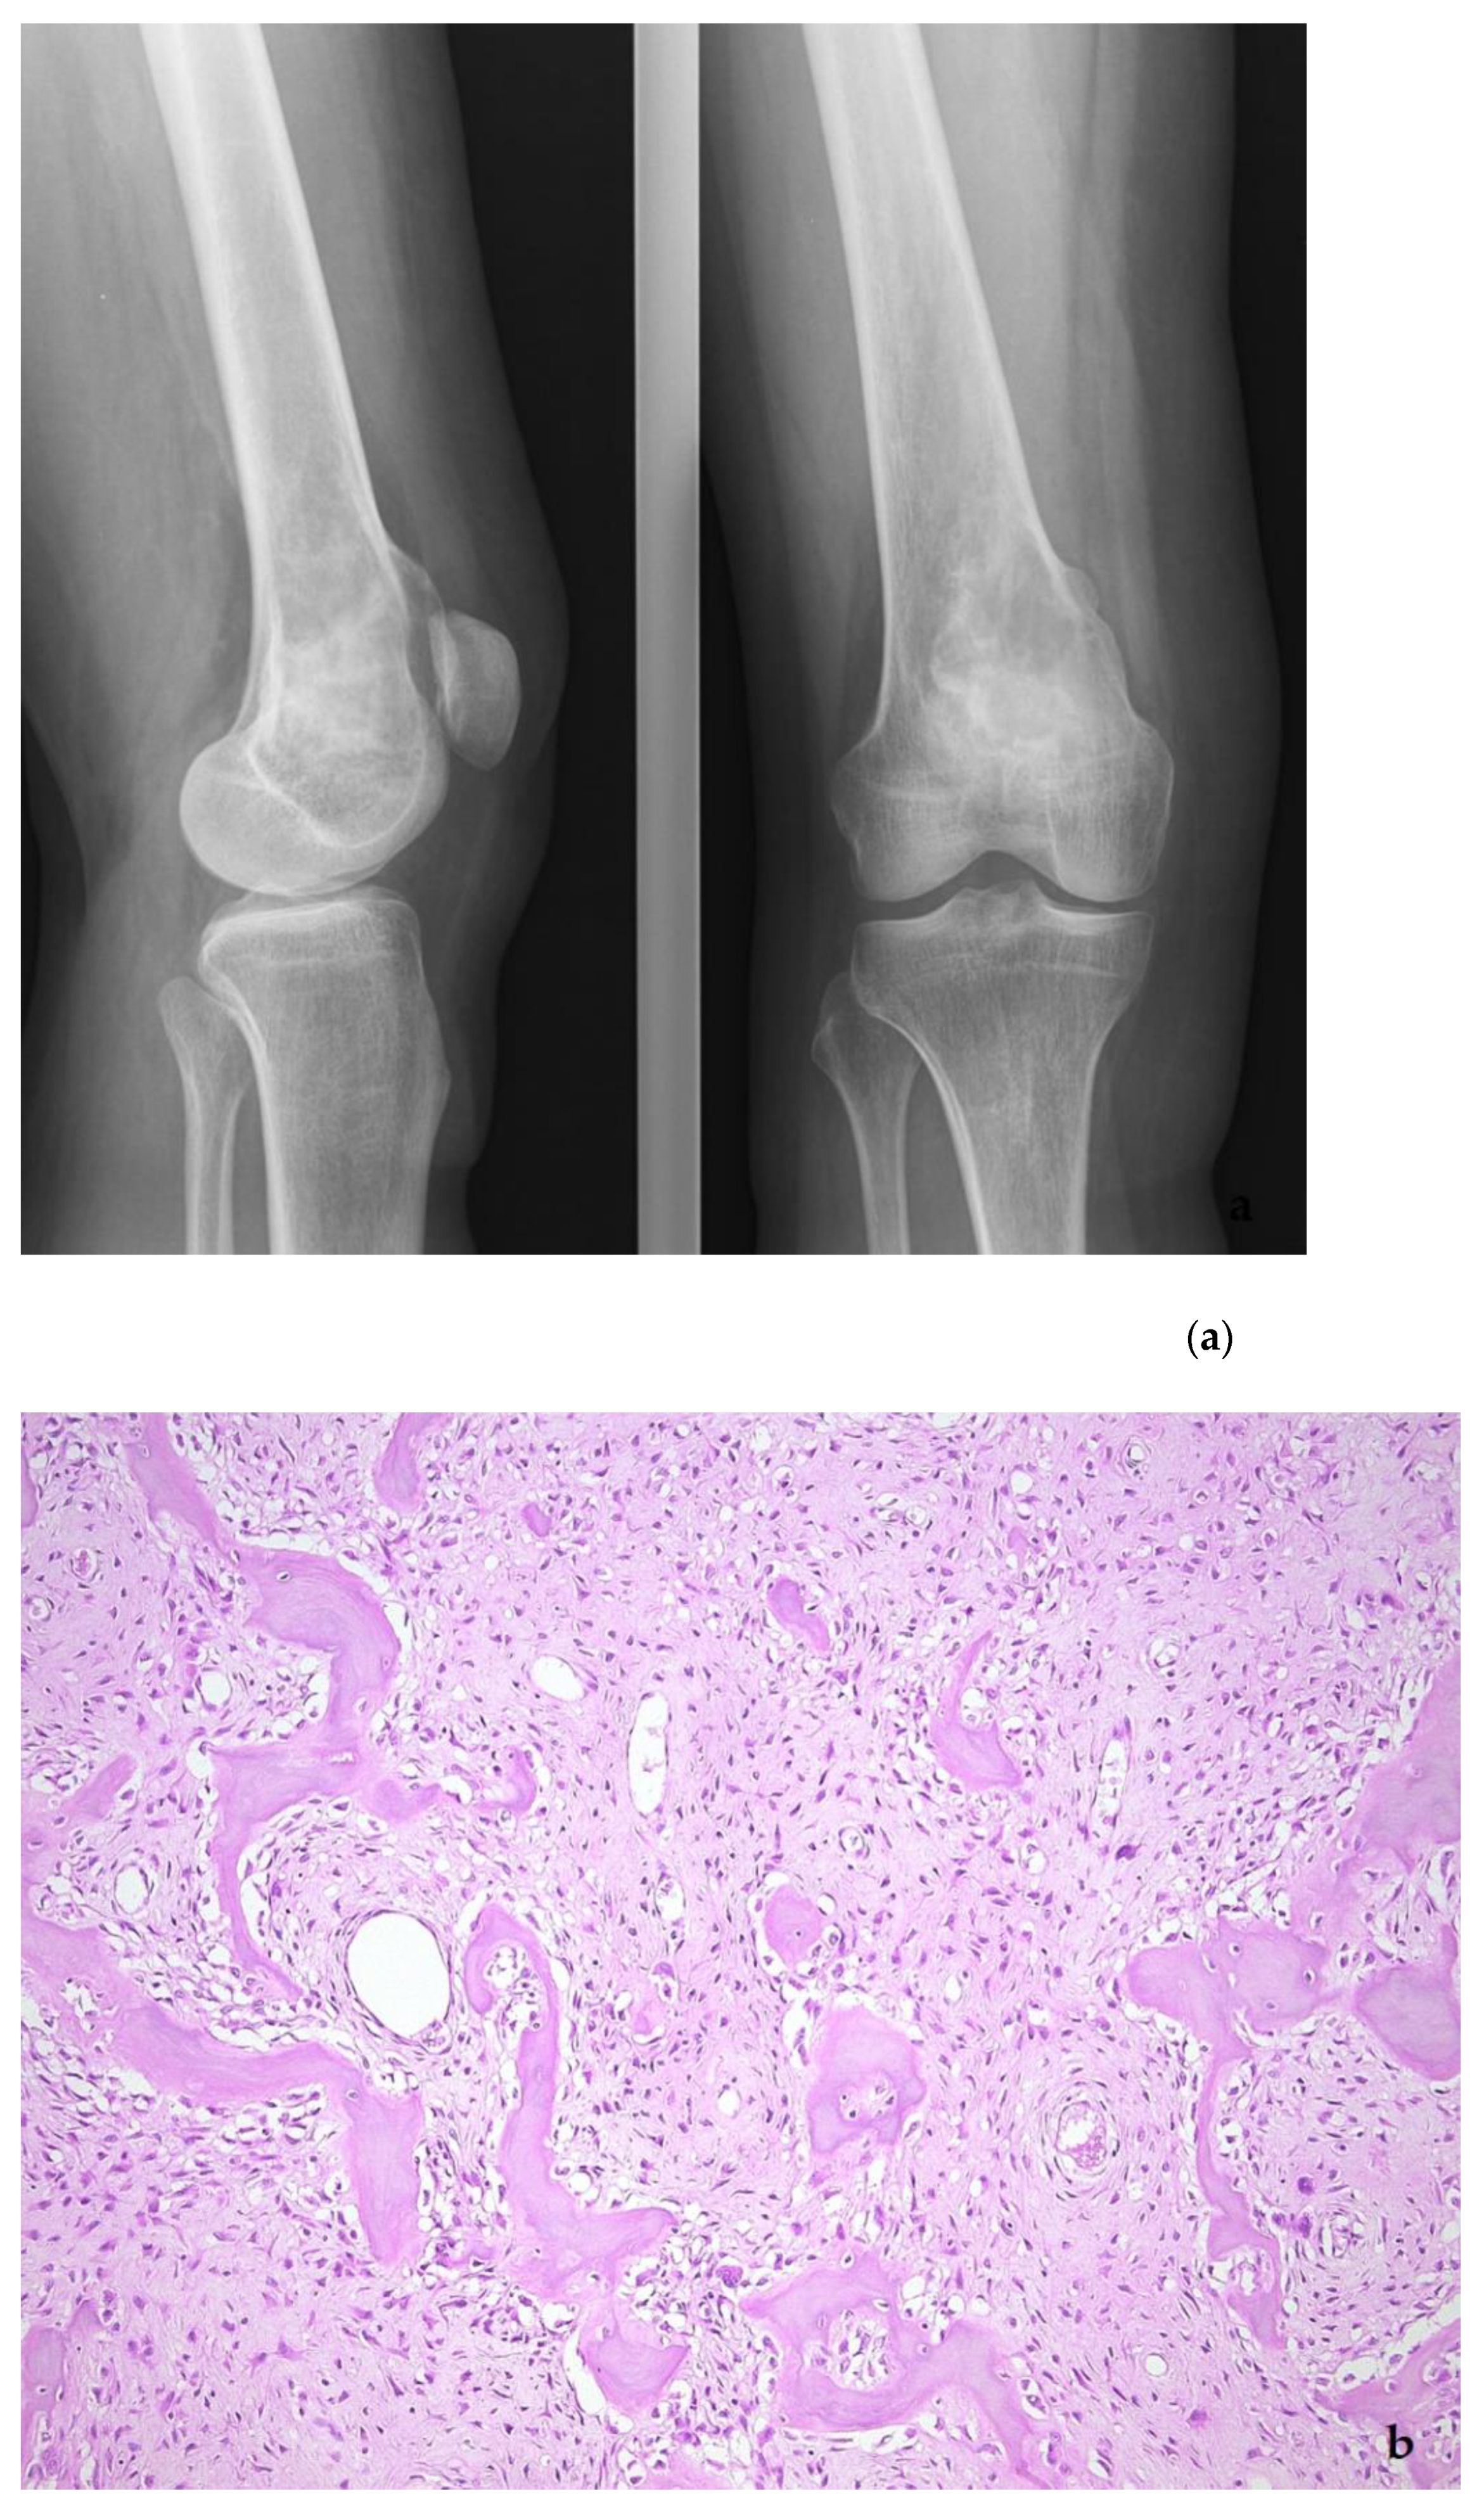

5. Low-Grade Osteosarcoma

- Dujardin, F.; Bui Nhuyen Binh, M.; Bouvier, C.; Gomez-Brouchet, A.; Larousserie, F.; de Muret, A.; Louis-Brennetot, C.; Aurias, A.; Coindre, J.M.; Guillou, L.; et al. MDM2 and CDK4 immunohistochemistry is a valuable tool in the differential diagnosis of low-grade osteosarcomas and other primary fibro-osseous lesions of the bone. Mod. Pathol. 2011, 24, 624–637. [Google Scholar] [CrossRef] [PubMed]

- Yoshida, A.; Ushiku, T.; Motoi, T.; Beppu, Y.; Fukayama, M.; Tsuda, H.; Shibata, T. MDM2 and CDK4 Immunohistochemical Coexpression in High-grade Osteosarcoma: Correlation with a Dedifferentiated Subtype. Am. J. Surg. Pathol. 2012, 36, 423–431. [Google Scholar] [CrossRef] [PubMed]